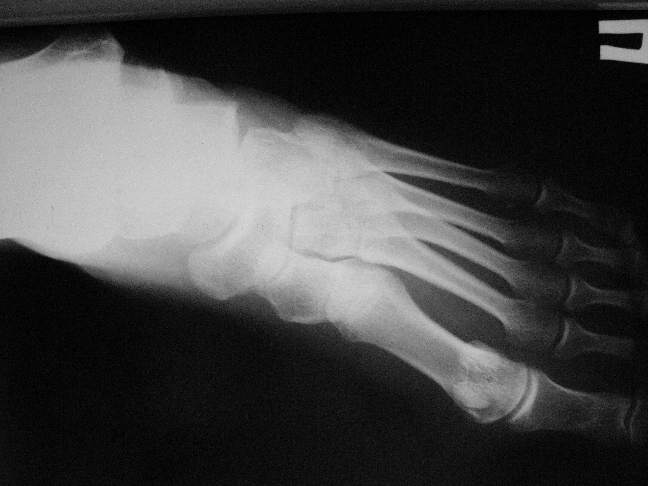

Справа перелом таранной кости со смещением  и мыщелка бедра без смещения,

посылаю дополнительные проекции.